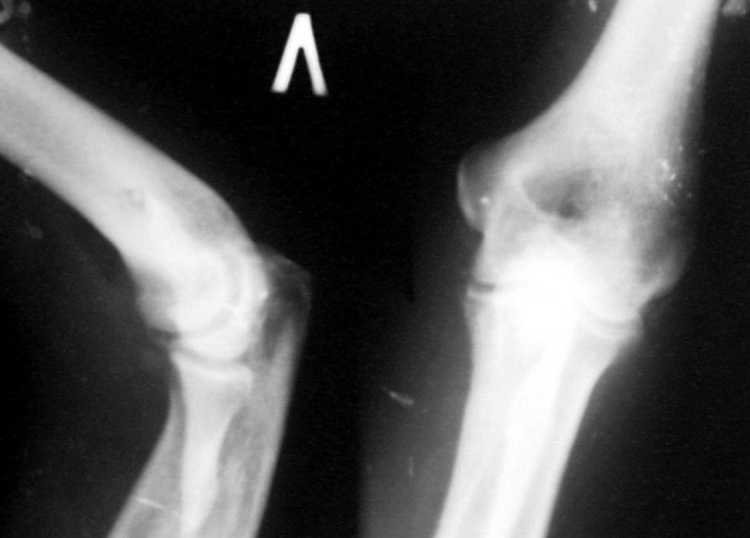

Поступил пациент, 47 лет. травма 15 сентября - вывих предплечья, репозиция. Фиксация 1 месяц. До настоящего времени не обращался. Вот рентенограммы на 2-й и 3-й месяцы после травмы. Неврологии нет. Имеется контрактура локтевого сустава (сгибиние 90, разгибание 120). На снимках что-то похожее на гетеротопические оссификаты, такое впечатление. Как лучше восстановить функцию, возможно ли применить редрессацию? Все-таки локтевой сустав "капризный".С ув. Sergey Melashenko, г. Запорожье

Для суждения о гетеротопических оссификациях нужны снимки хорошего качества, а не то, что есть. Или преобразуйте их в photoshop.